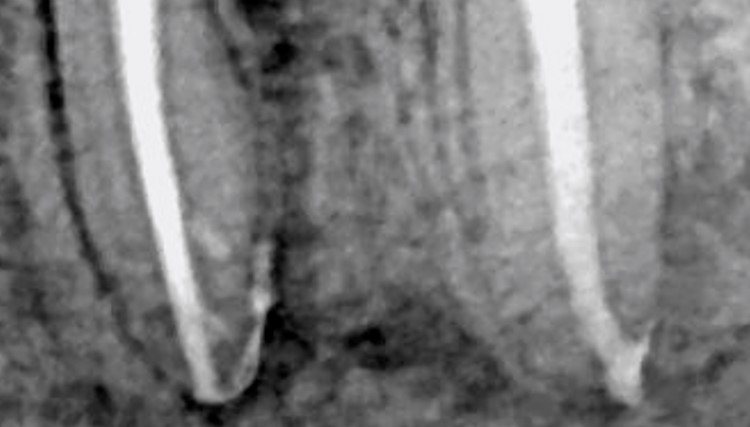

Pre-OP X-Ray

Tooth 36.

Patient was referred after persistant pain despite previous treatment attempts.

Post-OP X-Ray

The post-operative X-Ray demonstrates a well-condensed and anatomically complete obturation of the root canal system.